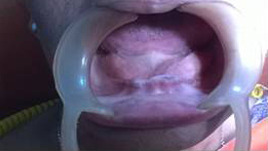

Suturing after Implant Placement

Use of Bone Graft & GTR membrane for an Implant

Before Placement of Prosthesis